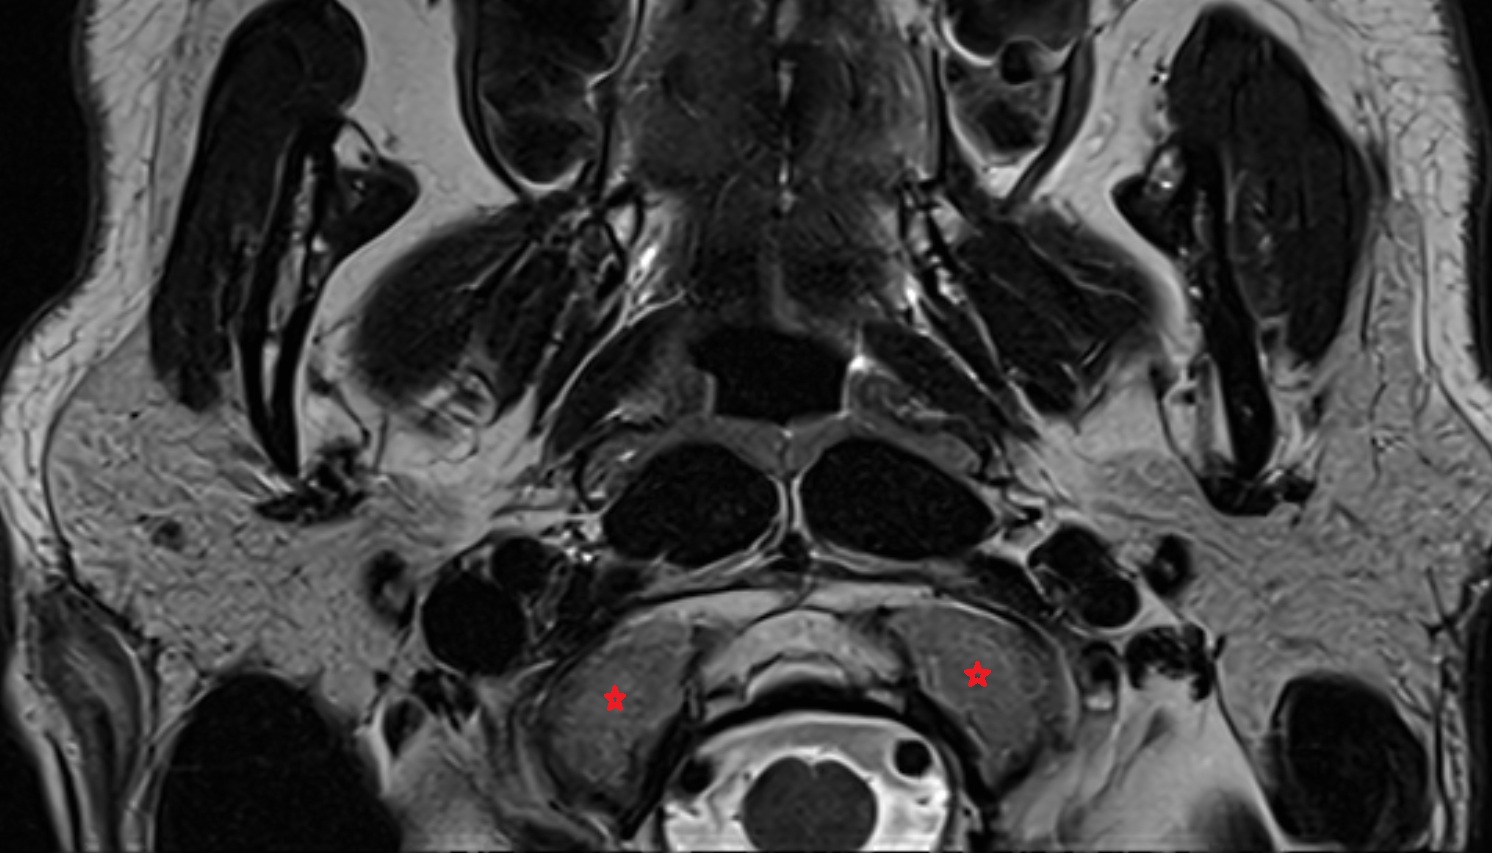

- Exiting nerve root of spinal nerve S1

- Traversing nerve root of spinal nerve S1

- Traversing nerve root of spinal nerve S2

- Traversing nerve root of spinal nerve S3

- Traversing nerve root of spinal nerve S4

- Exiting nerve root of spinal nerve S2

- Exiting nerve root of spinal nerve S3

- Exiting nerve root of spinal nerve S4